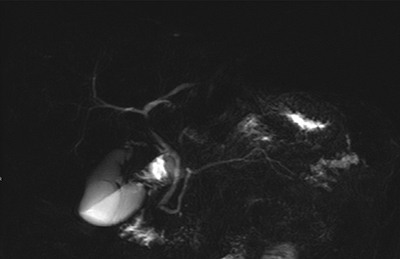

Figure 4

MR cholangiopancreatography, RARE sequence showing caudal division of the Wirsung duct and chronic pancreatitis changes.